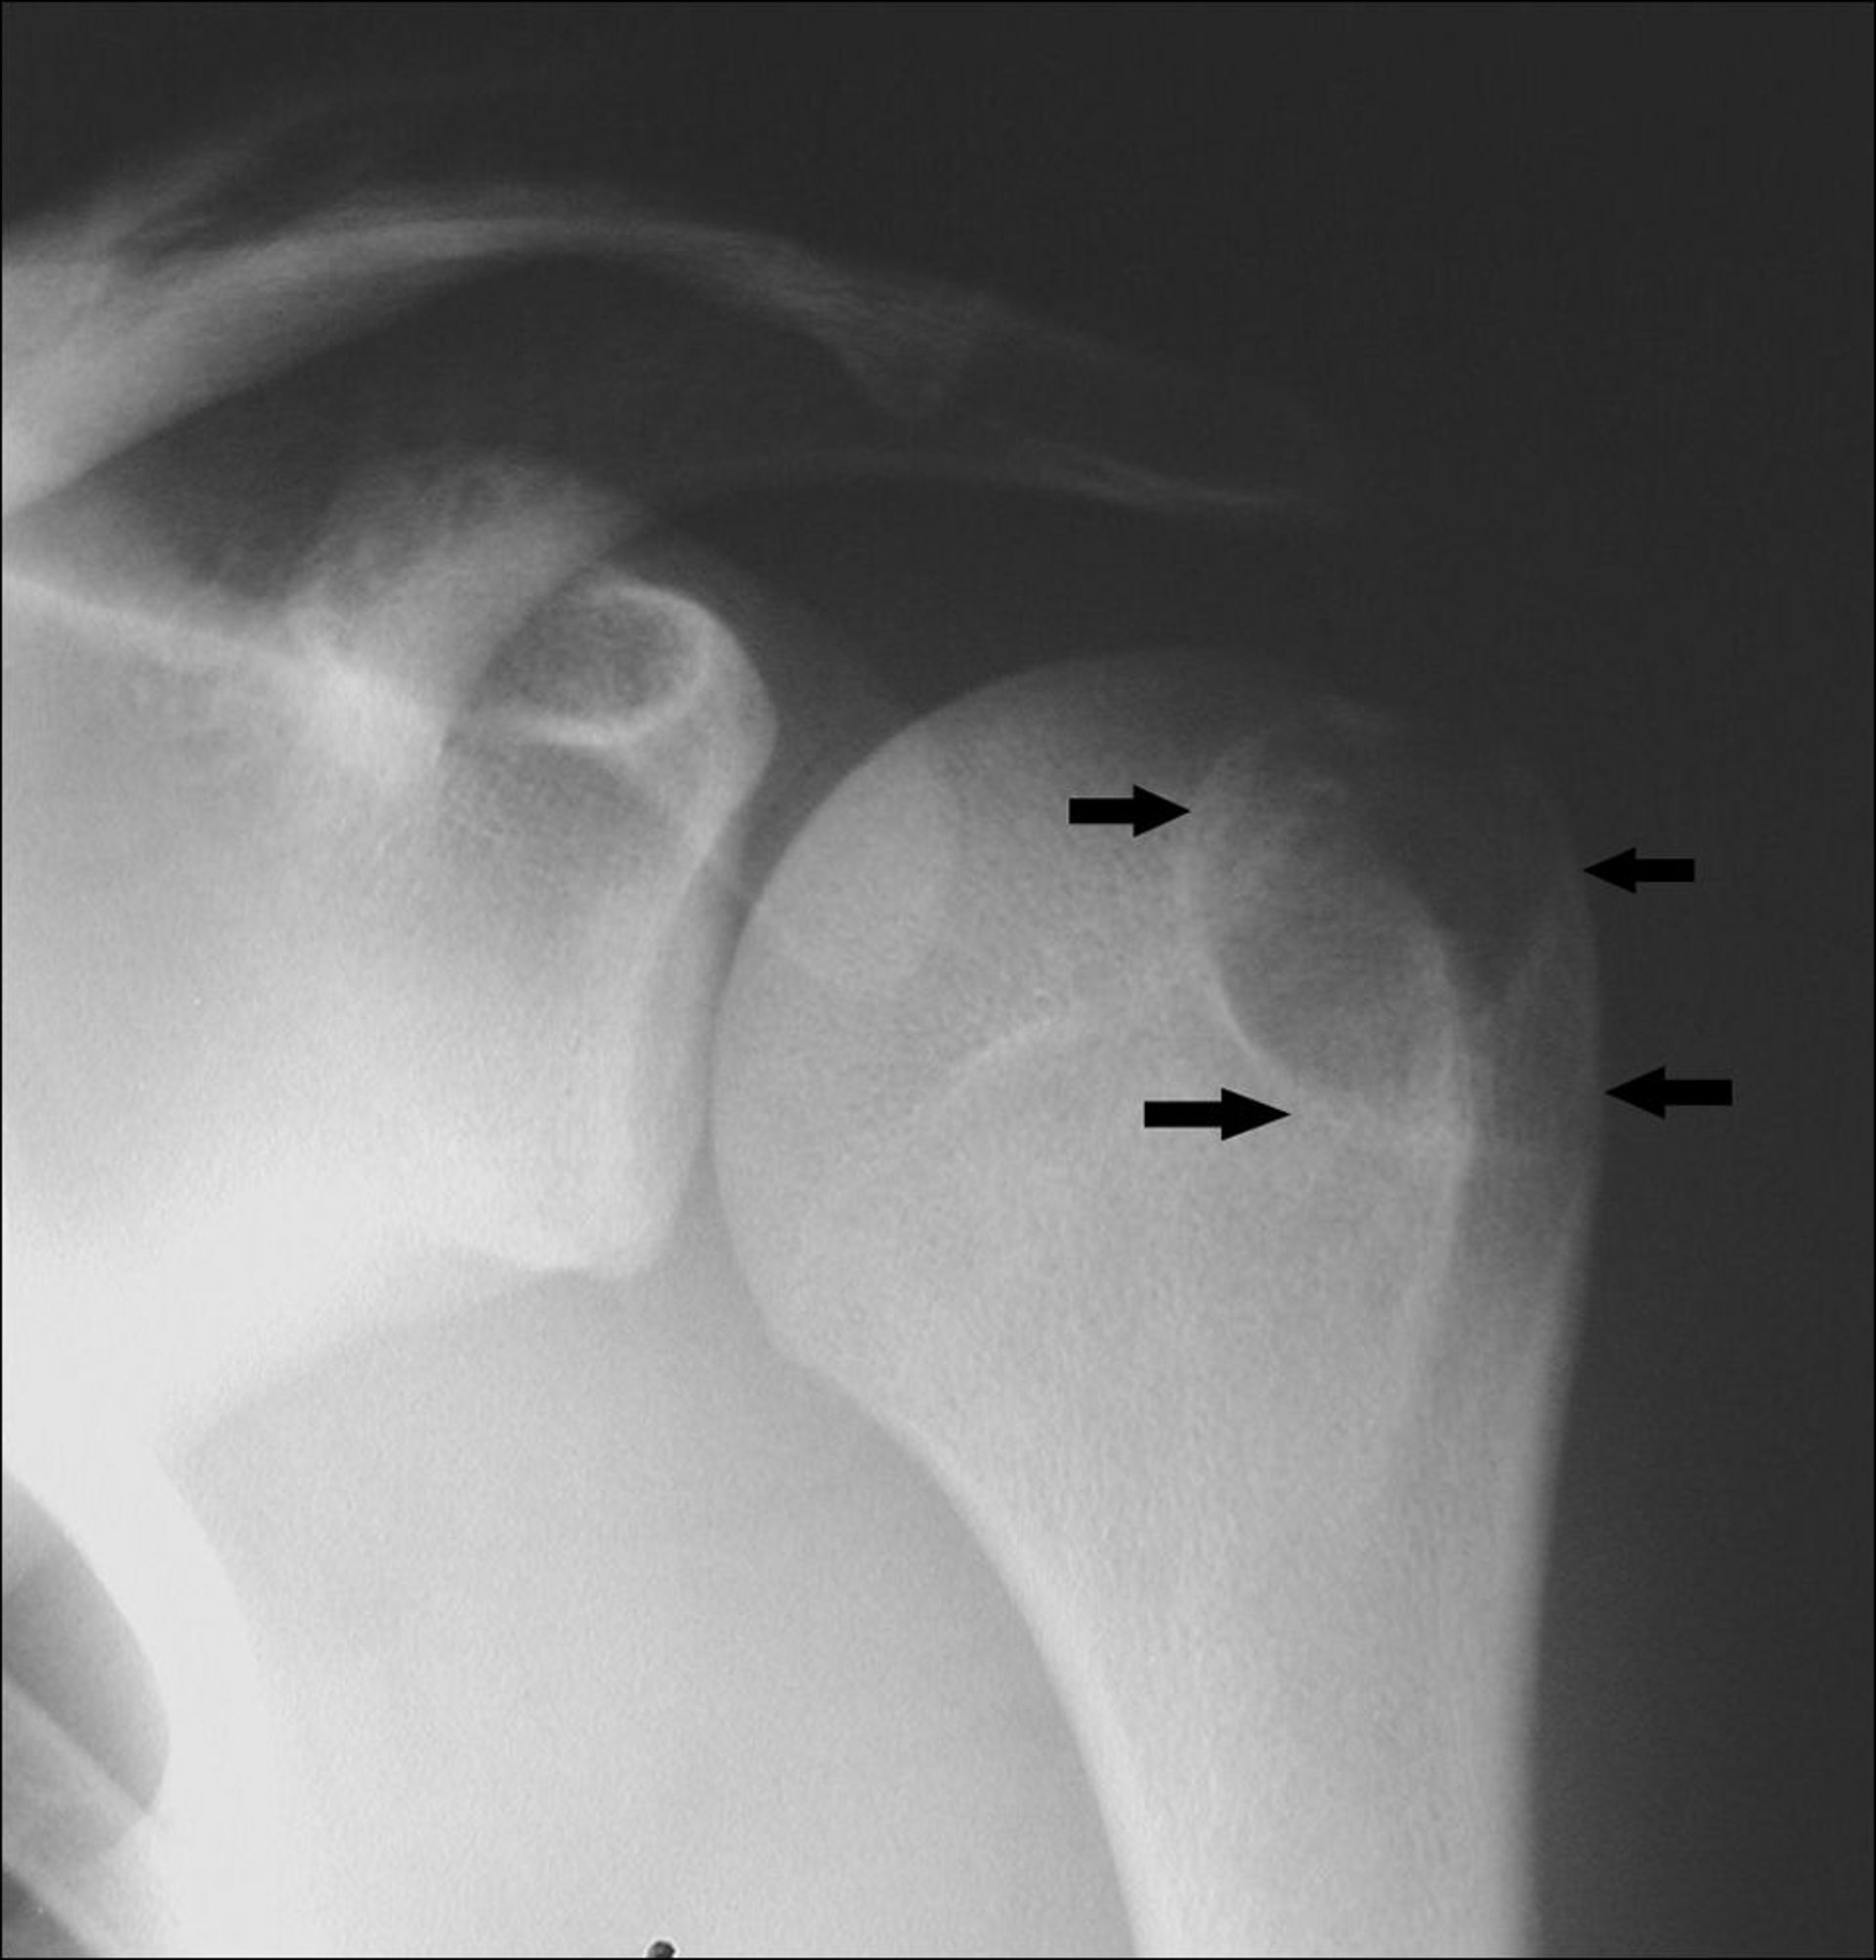

Esta radiografia do ombro evidencia um condroblastoma no úmero, localizado na apófise do tubérculo maior (setas).